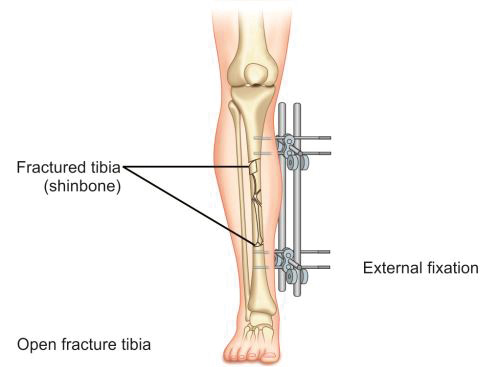

Immobilization by External Fixation

In this method, fractured fragments are anchored to an external bar with help of pins inserted into proximal and distal fragments of bone. Two or three pins are inserted into each fragment and connected to a rod or bar with help of clamps (Fig. 1.38). This method is mainly applied in cases of open and infected fractures where internal fixation carries a high risk of infection or its exacerbation. External fixator in this situation provides a stabilizing assembly that simultaneously allows dressing of the wound and since most of its assembly is outside the skin, there are least chances of infection. Commonly used external fixator frames are one plane (monolateral) frame, two plane (bilateral) frame and ring fixator.